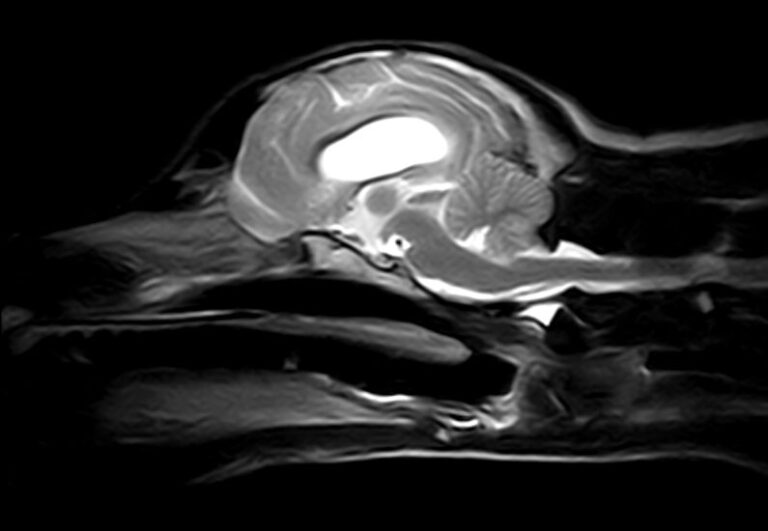

Diagnóstico avanzado: La excelencia en la neurología veterinaria exige tecnología de vanguardia. Usamos resonancia magnética y TAC para obtener imágenes de alta precisión.

Patologías diagnosticada por RM y TC:

Hernias discales

Masas intracraneales

Lesiones medulares

Meningitis y procesos inflamatorios

Infartos cerebrales